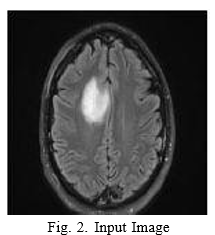

Let us consider the brain tumor image procured from MRI, containing the tumor in Fig.2.

Median filtering is applied on the input image to get rid of the unwanted noises. The output image is displayed in the Fig.3.